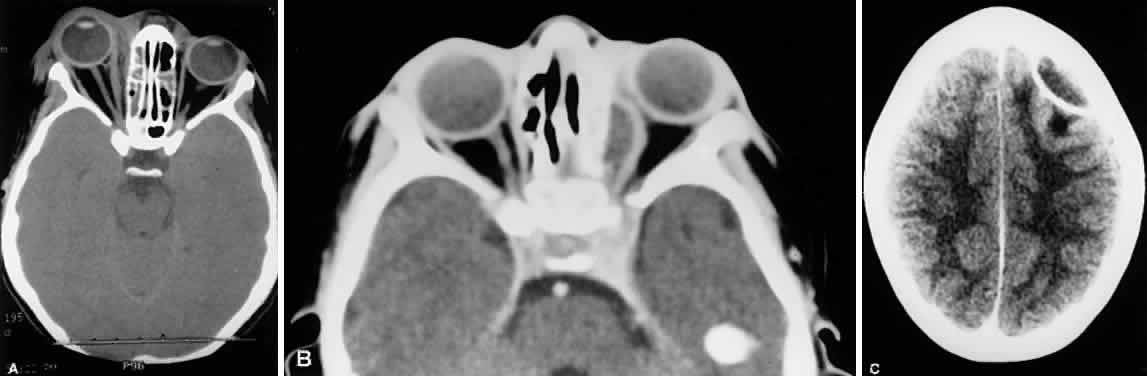

Surgical drainage of the sinuses should be considered if the clinical response to conventional high-dose antibiotics is poor or if the sinuses are completely opacified on the CT scan. Craniotomy is indicated if brain abscesses develop and do not quickly respond to systemic antibiotics. Orbital surgery with or without sinusectomy must be considered in every case of subperiosteal and intraorbital abscess formation, but many apparent abscesses resolve with antibiotics alone. Inflammation along the medial wall of the orbit with displacement of the medial rectus muscle but without distinct abscess formation on CT scanning is termed a phlegmon (Fig. 24). Phlegmons usually resolve with systemic antibiotic therapy without progressing to abscess. A subperiosteal abscess, most commonly located along the medial wall of the orbit, need not always be surgically drained. Such drainage is definitely indicated, however, if (1) an afferent pupillary defect develops; (2) vision decreases; (3) there is severe or progressive proptosis despite adequate antibiotic therapy; or (4) a follow-up CT scan shows no reduction in the size of the abscess after 48 to 72 hours of adequate intravenous antibiotics.61–64 Surgical drainage carries a low morbidity; delay of drainage, when appropriate, may be disastrous.65 True intraorbital abscesses (outside the subperiosteal space) are relatively unusual with sinusitis and occur more commonly with penetrating orbital trauma. Abscesses so located are sometimes called intraconal, denoting their presence within the periosteal cone of the orbit; it must be made clear that the term intraconal in this context does not refer to the cone formed by the rectus muscles and their intermuscular septa. Any purulent material collected from the subperiosteal space, sinuses, or intraorbital abscesses should be submitted for Gram's stain and for inoculation to aerobic and anaerobic media. If a subperiosteal abscess is small, if the visual acuity remains normal, and if no afferent pupillary defect develops, surgical exploration can usually be deferred.66–70

Fig. 24. A. Phlegmon of the medial orbit due to ethmoid sinusitis. There is no distinct abscess cavity. Note swelling and displacement of the medial rectus muscle. B. Subperiosteal abscess. C. Intracranial abscess secondary to ethmoid sinusitis with orbital cellulitis.